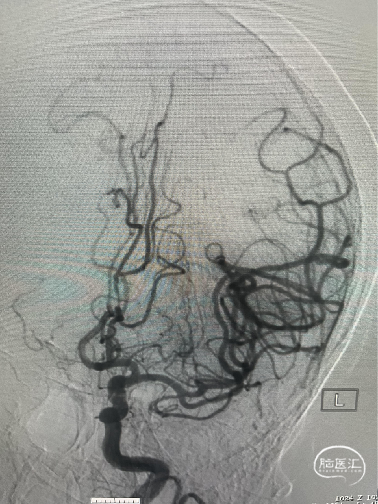

Trevo 6mm×25mm支架释放:

Trevo 6mm×25mm支架释放,全程显影,正位造影提示支架打开。

SWIM技术取栓:

SWIM取栓后,血管再通,无栓子逃逸,闭塞局部无血管狭窄。